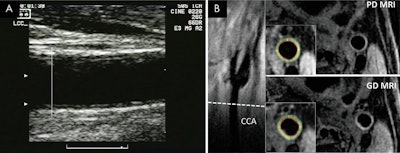

Participants initially underwent ultrasound and MRI exams between 2000 and 2004 to assess carotid artery wall thickness. MRI protocols included gadolinium-enhanced and noncontrast proton-density-weighted scans on 1.5-tesla systems with bilateral dedicated carotid coils at all six MESA sites.

By comparison, MRI can image the circumference of the entire vessel wall, including the adventitia, or outer-most layer, which is not visible on ultrasound. The adventitia also is where small vessels proliferate, which could progress to thickening of the artery and result in vascular inflammation and disease.

In fact, MRI measurements with or without contrast were better than ultrasound measurements based on manual intima-media thickness for predicting coronary artery disease, stroke, and cardiovascular disease. The key difference is MRI's ability to image the thickness of the entire carotid vessel wall, which ultrasound cannot do.